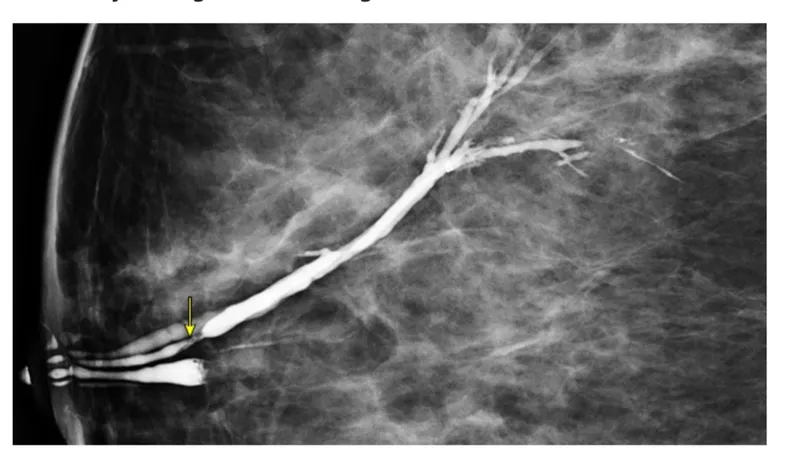

- Initial workup for pathologic discharge includes mammography and ultrasound, particularly in women >30.

- If imaging is negative but discharge remains suspicious, terminal duct excision is diagnostic.